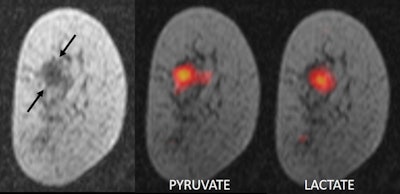

Tumors make use of large amounts of sugar and take up more pyruvate than normal tissue, explained team member Dr. Ramona Woitek, PhD, from the University of Cambridge. Inside the tumor, pyruvate is converted into lactate as part of a natural metabolic process. Since magnetizing the carbon-13 pyruvate molecules increases the strength of the MRI signal by 10,000 times, the researchers can monitor this process and visualize it dynamically in MRI scans.

The rate of pyruvate metabolism -- and the amount of lactate produced -- varies not only between different tumors but also between different regions of the same tumor. By monitoring this conversion in real-time, the researchers said they are able to determine the type of cancer being imaged. They can also determine how aggressive a tumor is, as faster-growing tumors convert pyruvate more rapidly than less-aggressive ones.